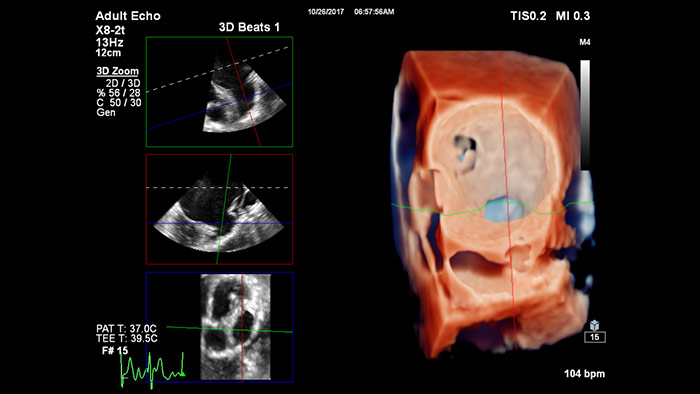

TrueVue du rendu 3D Zoom pour l’appendice auriculaire gauche avec visualisation MultiVue

Visualisation TrueVue de la réparation mitrale bord à bord

Visualisation de la réparation mitrale de la régurgitation post-implant